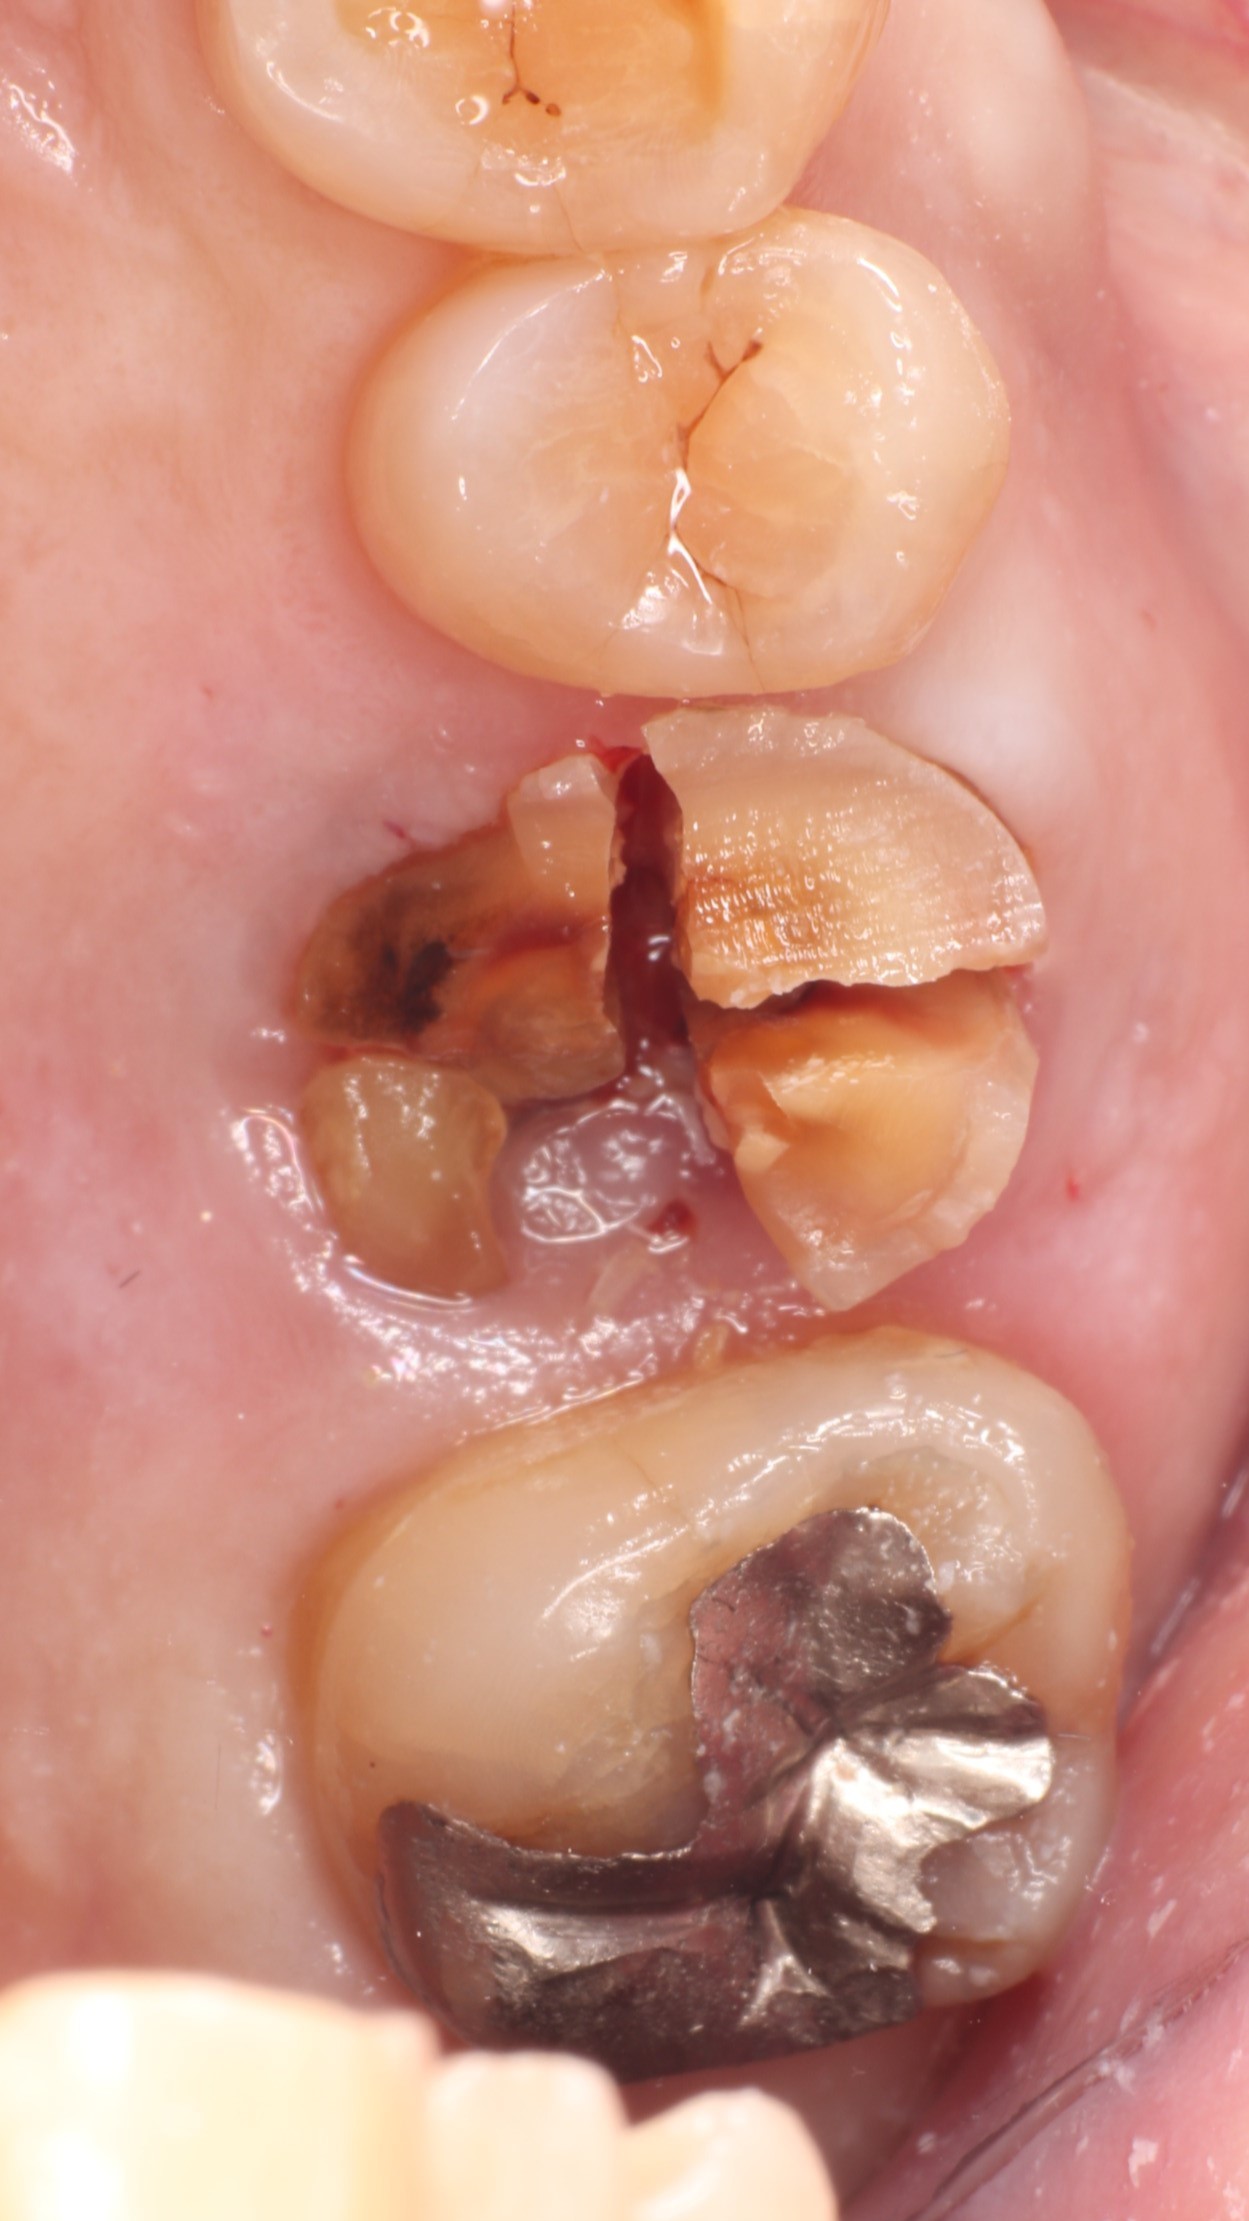

Step 1 破折した歯を丁寧に抜歯

根破折した上顎大臼歯

歯根が破折しており、保存困難と診断しました。上顎洞に近接した部位のため、一般的には「骨を足す手術が別途必要」「抜歯後、骨が治癒してから数か月後にインプラント埋入」と説明されることも多いケースです。

Step 2 抜歯直後

抜歯直後の抜歯窩

丁寧な抜歯処置により骨壁を温存。抜歯窩の形態を確認し、同日のインプラント埋入が可能と判断しました。切開・縫合の範囲を最小限に抑えることで、術後の腫れや痛みを軽減します。